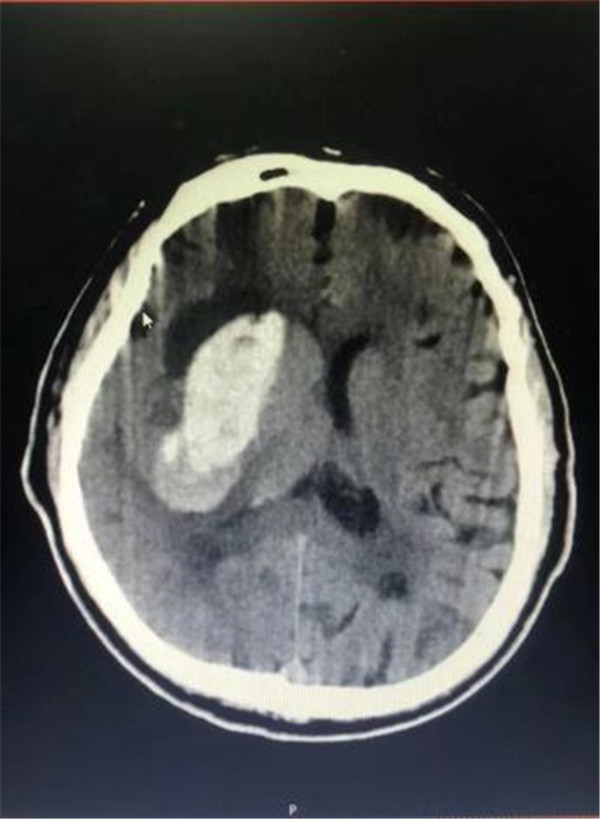

术前CT片 出血量约50ml

该手术是采用了国内首台脑出血手术机器人——睿米RM50来导航。有了这位“智能助手”的帮忙,大大缩短了手术时间,手术过程非常顺利,术后血肿大部分引出,目前,患者体征平稳,恢复良好。该术式达到了微创伤、精准定位、安全高效地对出血性中风病人的脑内血肿定位,穿刺抽吸血肿的治疗目的,同时能一定程度上改善保守治疗时脑内血肿长期压迫所致的神经损伤症状。